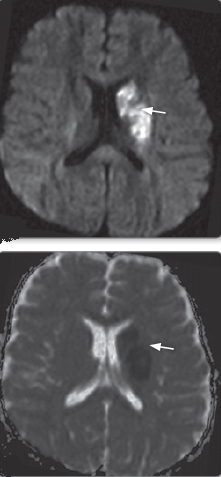

- โก DWI/ADC: Bright in acute ischaemic stroke (cytotoxic oedema).

| ๐ Acute Ischaemic Stroke | DWI bright (acute), ADC low; FLAIR/T2 hyperintense after few hours; GRE may show thrombosis. |

| DWI | ADC |

|  |